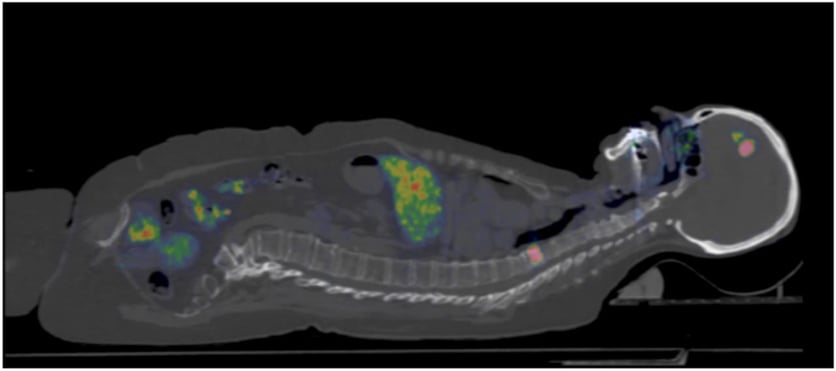

I september inleds en stor nordisk studie vars främsta mål är att med hjälp av pet-kamera se vilken typ av bröstcancer patienten har och därmed kunna anpassa behandlingen mer individuellt. Forskarna använder en metod som utvecklats vid Uppsala universitet och pet-centrum på Akademiska sjukhuset som gör det möjligt att upptäcka om kvinnan har så kallade HER2-positiva metastaser.

Den nya pet-metoden innebär att man använder ett litet protein/spårämne, en så kallad affibody, som kopplas till radioaktivt Gallium på pet-centrum vid Akademiska sjukhuset. Proteinet fungerar som målsökare och fäster vid HER2-proteinet. Proteinet sprutas in i ett blodkärl och transporteras vidare till resten av kroppen. När det fastnar i vävnader med mycket av HER2-protein kan pet-kameran läsa av radioaktiva signaler.

• Syftet är att med hjälp av ett radioaktivt märkt spårämne, affibody, och pet-kamera se om patienterna har HER2-positiva tumörer, vilket har stor betydelse för valet av behandling.

• Spårämnet som används är ett litet veckat protein kallat affibody, som utvecklats av Affibody AB i samarbete med forskare på Uppsala universitet och Akademiska sjukhuset. Proteinet fungerar som målsökare och fäster vid HER2-proteinet vilket signaleras till pet-kameran.

Effektivare diagnostik av bröstcancer utan biopsier är målet för en nordisk studie ledd från Akademiska. Forskarna använder pet-kamera och ett nytt spårämne.